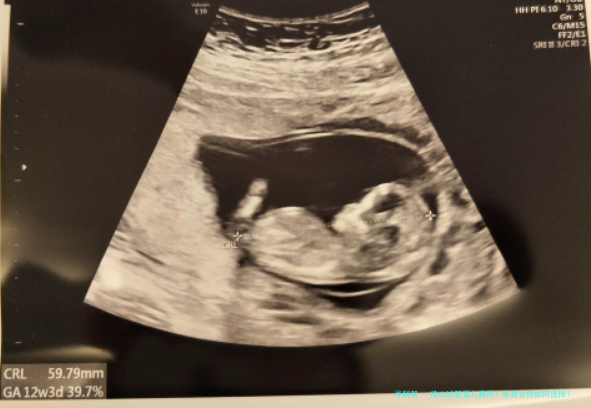

在佛山,独身女性做试管婴儿时,大部分条件下需要获得助试管的形式来完成。进行试管受孕,最终将胚胎移植到独身女性的肚子里。